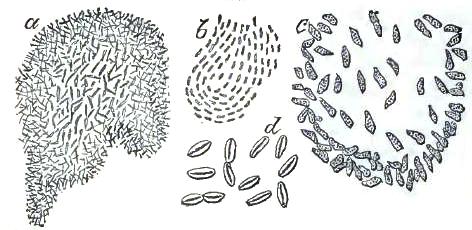

| FIGURE | |

| 1. | MICROCOCCI |

| 2. | BACTERIA |

| 3. | BACILLUS MALARIÆ |

| 4. | BACTERIA FROM GELATIN SOLUTION |

| 5. | VIBRIOS IN GELATIN CULTURE-FLUID |

| 6. | PROTOCOCCUS FROM SLIDES EXPOSED OVER SWAMP-MUD |

| 7. | BACILLI FROM SWAMP-MUD |

| 8. | BACILLI FROM SEPTICÆMIC RABBIT |

| 9. | BACILLI FROM HUMAN SALIVA |

| 10. | BACILLUS ANTHRACIS |

| 11. | BACILLUS TUBERCULOSIS |